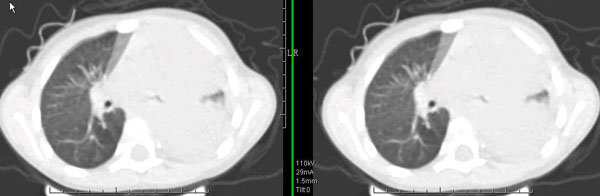

男孩,4岁,发热咳嗽4天。

下面补充ct图片:

此病人是我接手的,发热、咳嗽来做胸透,透视见左侧肺野大部密实,纵隔、心影明显左移,呼吸示纵隔摆动、膈肌矛盾运动(透视下采集了几幅图片),左肺动度明显减弱。询问病人家长,没有吃花生米等呛咳史。由于其影像特征明显,当时诊断:考虑左侧支气管异物并阻塞性肺不张、肺炎。

病人去上级医院支气管镜取出了异物。今天询问上级医院耳鼻喉科主任(是我同学),得知病人异物为胶冻样合并有少许白色粉末,后小儿说晚上喝药片时呛咳过,考虑当时为药片阻塞;另外支气管镜检发现小儿左侧支气管发育略窄,经住院抗炎治疗,现病人基本康复。

多谢各位关注及精彩点评!追踪病人结果时才知道还做过ct检查!对不起!有点晚了,刚刚下载,上传供大家参考!